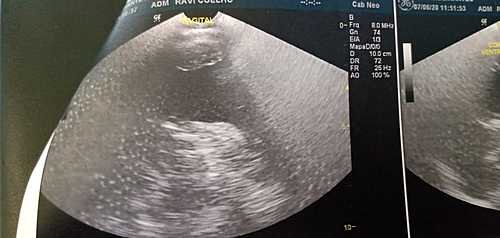

Sou a Rafaelli mãe do Ravi! Vou contar a história do meu filho. Ravi atualmente está com 6 meses, nasceu lindo e saudável, passando os dias, percebemos que nas suas fezes começou a sair sangue, entre idas e vindas de medicos, descobriramos que ele é APLV, e também é alérgico à outros alimentos (carne vermelha, ovos, trigo, algumas frutas e legumes), poucos meses depois, levei Ravi ao pediatra em uma consulta de rotina e descobriu que ele tem também Nistagmo na vista, então a médica o encaminhou para uma oftalmologista e um neurologista, saímos das consultas com mais exames , pois a neurologista pediu urgentemente 1 Ultrassonografia tansfontanela, pois com apenas 4 meses a moleira dele já havia se fechado e a testinha dele está formando um triângulo para a preocupação de todos. A médica suspeitou de craniostenose, uma deformidade no crânio muito sério que precisa de cirurgia para correção, antes que o bebê venha ter sequelas irreversíveis . Sendo assim com arrecadações de doações e também venda de rifa, conseguimos juntar o dinheiro do exame da fontanela, e foi constado que realmente ele tem a craniostenose, e também para nossa surpresa Hidrocefalia. Vamos fazer agora uma TC do crânio e TC das órbitas (oftalmologista pediu, pois há um esbranquiçado em uma delas) para irem mais a fundo do quadro e saber quando e como vão fazer essa cirurgia. Não temos condição de arcar com todos os custos, essas TC o plano não cobre por causa da carência, e pelo SUS sem data para realizar os exames, então terei que pagar, tenho também o gasto da minha alimentação, que é muito alto o custo, mais preciso ter uma alimentação saudável ,pois eu ainda amamento, além do leite especial que ele tem que tomar NEOCATE, que graças a Deus consegui pegar os papéis para dar entrada pelo governo e pegar sem custo dia 23 de outubro a consulta para pegar os leites, tem o dinheiro entre idas e vindas ao médico, agora também temos esses exames para realizar as TC do Crânio , e TC dá órbitas . Peço encarecidamente para vocês nos ajude com a quantia que for, vou ser grata eternamente. Desde já agradeço por toda atenção.